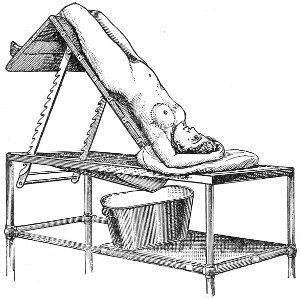

Examination of External Genitals and Pelvic Structures.—To examine the external organs of generation and the pelvic viscera the woman should be placed upon a table. In some cases the physician may be obliged, for want of proper facilities or on account of the physical condition of the patient, to make his examination upon a bed. Such an examination, however, is never so satisfactory or so thorough as the examination made with the woman upon the examining-table. A great number of gynecological tables have been introduced. The one which seems to the writer the best, on account of its simplicity and the perfect relaxation of the abdominal muscles furnished by it, is shown in the accompanying illustration (Fig. 1). It is a plain wooden table, at the foot of which are attached the upright supports for holding the stirrups for the feet, such as have been devised by Dr. Edebohls. By this arrangement the feet and legs are supported without any effort on the part of the woman; when the buttocks are drawn well down to the foot of the table there is a certain amount of flexion 23 of the pelvis upon the trunk, and the most complete attainable relaxation of the abdominal muscles is secured.

Fig. 1.—Woman in the dorsal position with feet supported in Edebohls’ stirrups.

For operation upon the perineum the woman should be placed in the dorso-sacral position (Fig. 1, page 23).